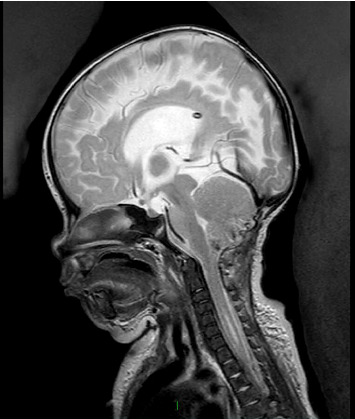

脊柱裂,特别是脊膜膨出,与自主神经功能障碍之间的联系是已知的,尽管罕见。本病例突出了脊髓脊膜膨出患儿继发的严重呼吸损害。我们描述了一个新生儿谁经历了严重的呼吸功能障碍后,成功的腰骶髓脊膜膨出修复在生命的第一天,在产前诊断为Arnold-Chiari II型畸形和先天性脑积水的背景下。此外,患者被发现有偶发脉络膜丛乳头状瘤,并在枕骨大孔减压术中切除。即使在多次成功的神经外科干预后,患者仍经历了多次需要插管和通气的呼吸暂停发作,并延长了重症监护病房的住院时间。尽管呼吸暂停-缺氧发作的频率异常高且严重,但患者表现出与年龄相适应的认知发展,现在通过气管切开术进行了夜间通气。围绕这些患者的多学科护理、呼吸窘迫的管理以及本病例的不同病因,我们可以吸取经验教训。尿路感染发作与呼吸暂停发作频率增加之间也存在相关性,这就提出了一个问题,即在有重要手术史的背景下,该患者的膀胱刺激是否部分触发了自主神经反射障碍。

The association between spina bifida, specifically myelomeningocele, and autonomic dysfunction is known although rare. This case highlights the severe respiratory compromise that can occur in paediatric patients secondary to myelomeningocele. We describe a case of a neonate who experienced profound respiratory dysfunction following a successful lumbosacral myelomeningocele repair on Day 1 of life, on the background of a prenatal diagnosis of Arnold-Chiari Type II malformation and congenital hydrocephalus. In addition, the patient was found to have an incidental choroid plexus papilloma which was resected along with foramen magnum decompression. Even after multiple successful neurosurgical interventions, the patient experienced a number of apnoeic episodes requiring intubation and ventilation and a prolonged intensive care unit stay. Despite the exceptionally high frequency and severity of the apnoeic-hypoxic episodes, the patient is demonstrating age-appropriate cognitive development and is now ventilated overnight via tracheostomy. There are lessons to be learnt surrounding the multidisciplinary care of these patients, management of respiratory distress, and the different aetiologies in this case. There was also a correlation found between episodes of urinary tract infection and increased frequency of apnoeic episodes, raising the question of whether her bladder irritation may be partially triggering her autonomic dysreflexia, on a background of a significant surgical history.